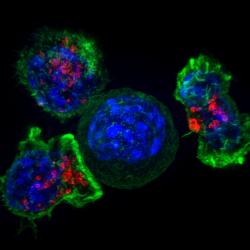

Азотфиксирующая бактерия, поселившись в водорослях, со временем стала внутриклеточной органеллой, связывающей атмосферный азот.

Микробы ротовой полости, пробираясь в желудок и кишечник, могут провоцировать в них возникновение и рост злокачественных опухолей.